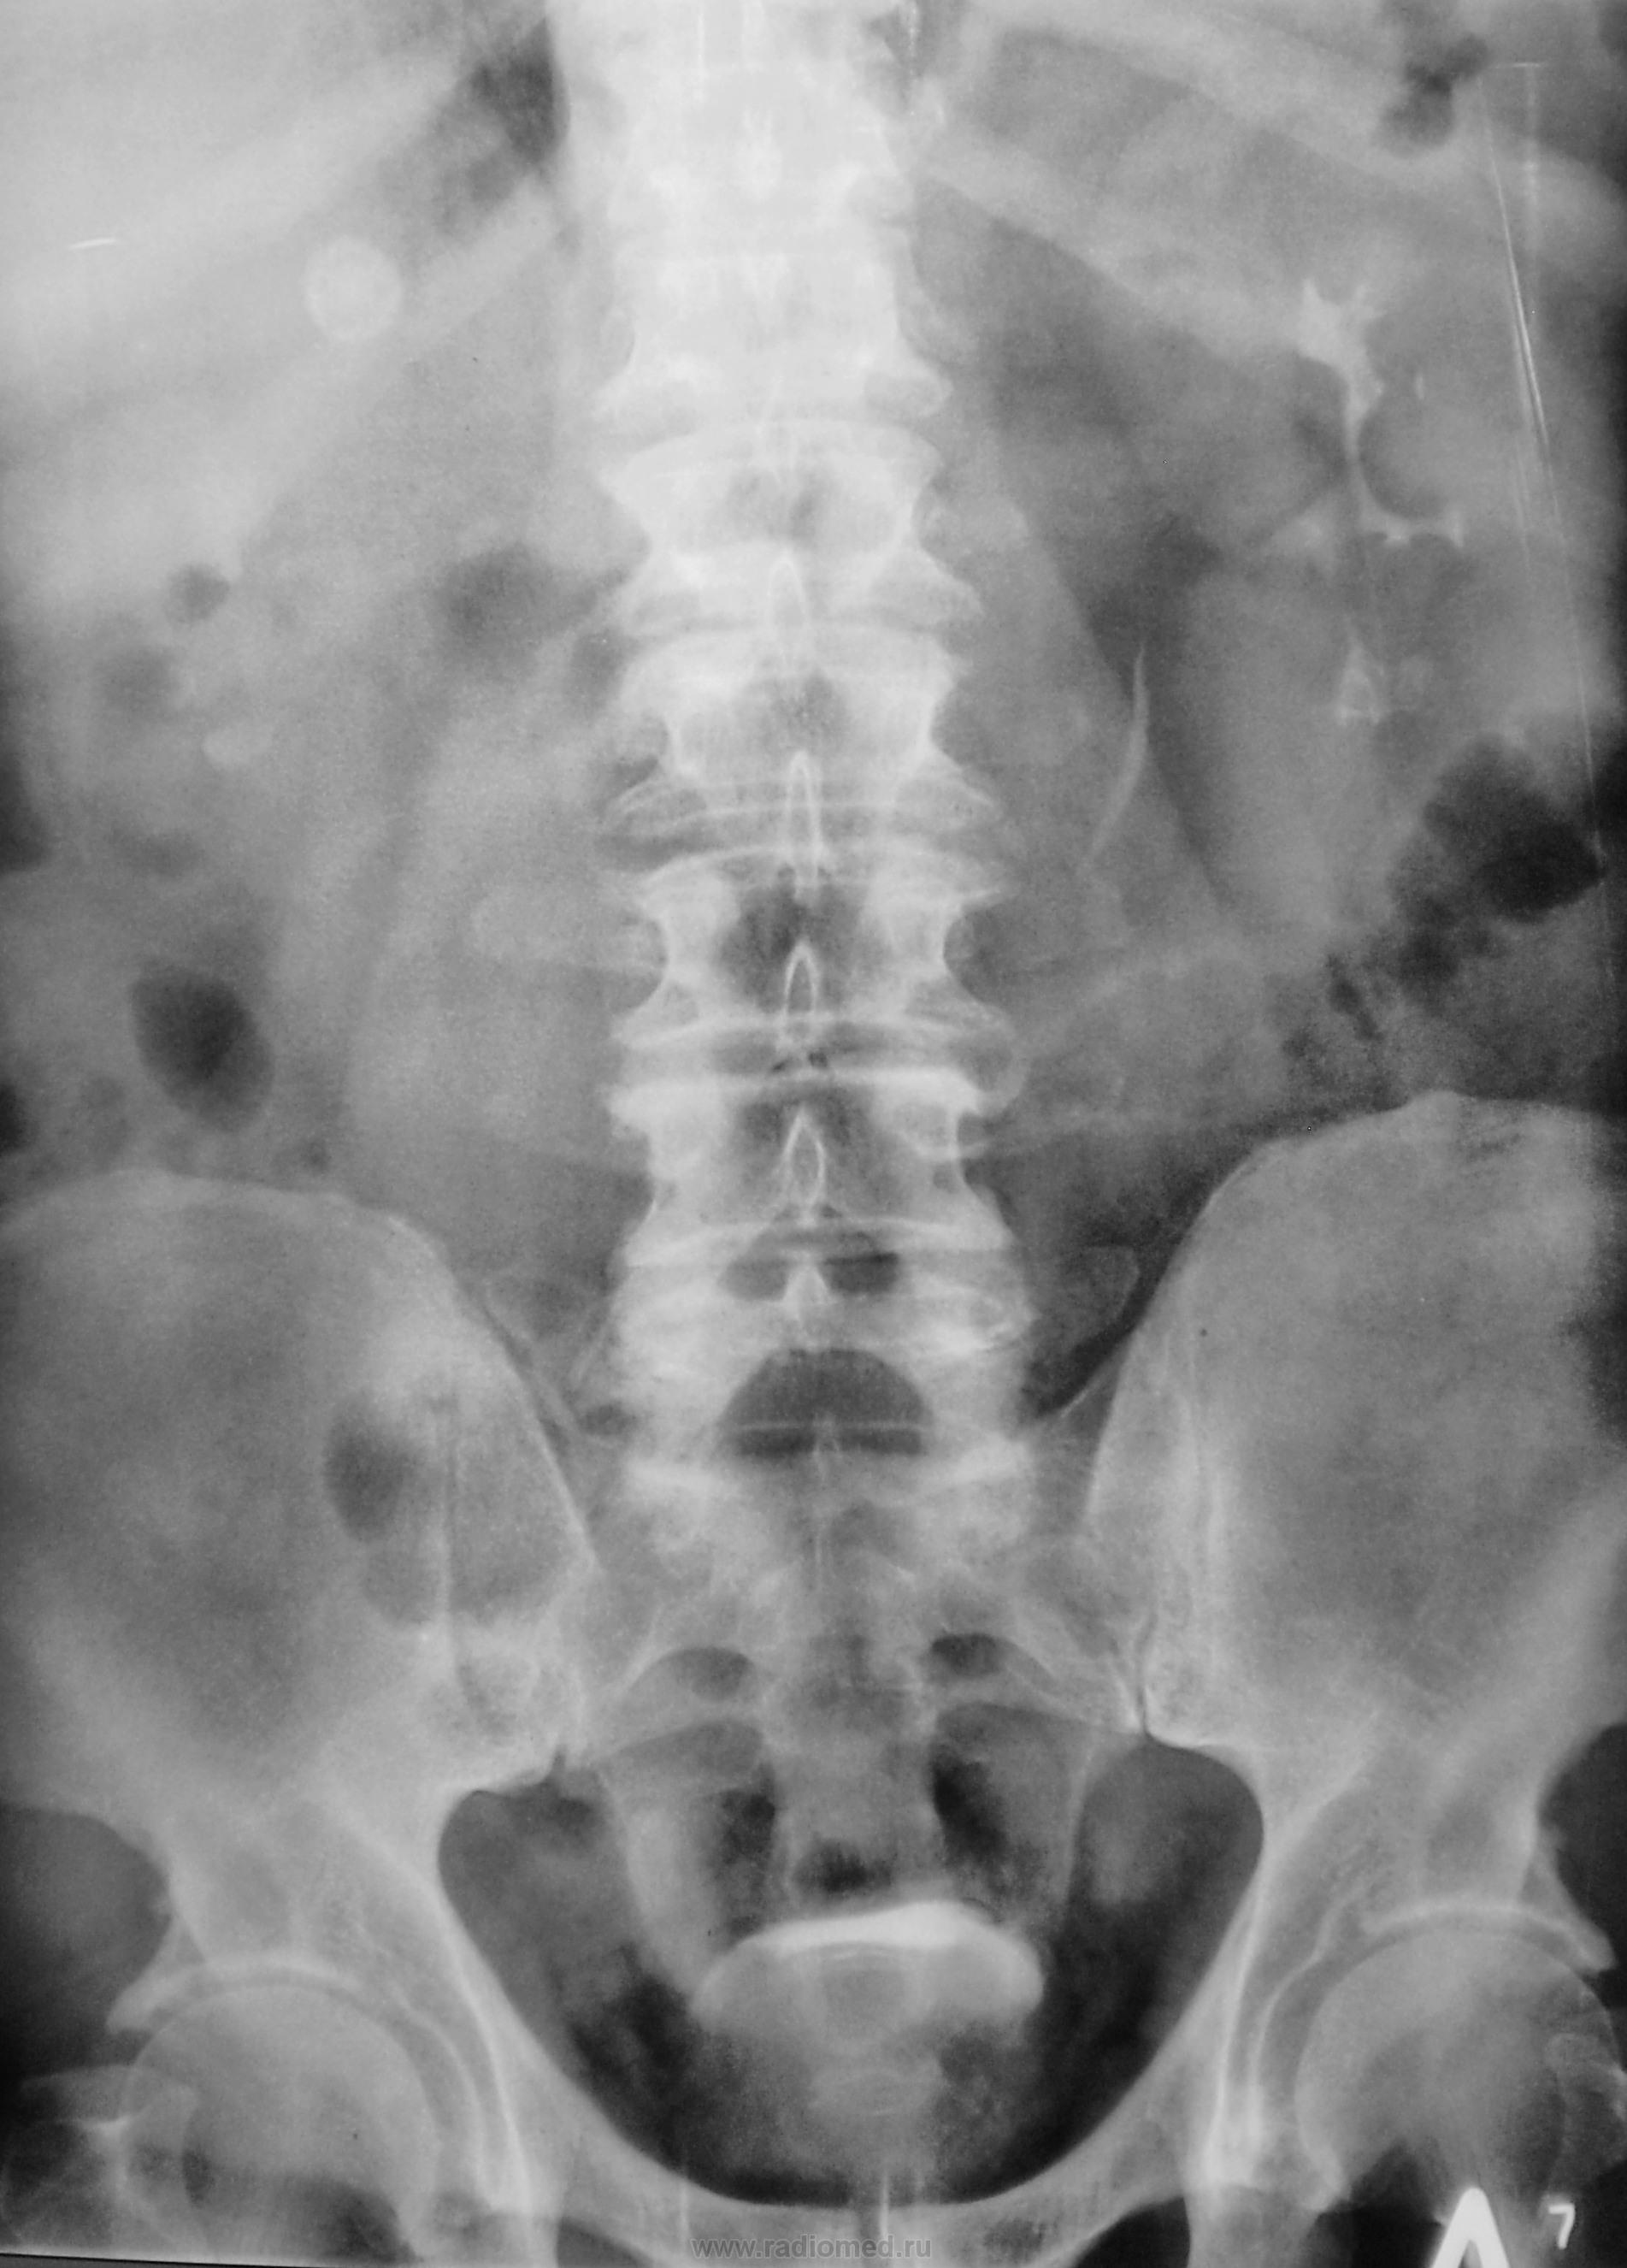

Признавайтесь, куда делась средняя треть правого мочеточника? Ее как-будто ножом отрезали под линейку, а ниже-сплошное безобразие! "ЧТО" может как обезобразить орган-банальная МКБ с частичной обтурацией просвета или опухоль? А в пузыре тоже камни?

Вы правы, камней не много, их - до "фига"...

Фи, доктор, это не латынь? Хотя можно выразиться и покрепче. Но в/в не дала ответов-где и что это?

А деформация мочевого пузыря никого не смущает?

Отчего же не смущает?))) смущает...она и есть первопричиной образования ТАКОГО камня в мочеточнике, теперь об этом можно сказать с уверенностью, ее генез - выраженое увеличение размеров простаты.